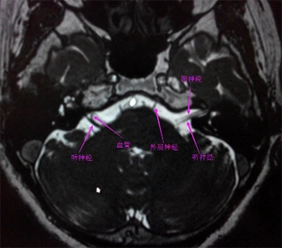

面神经解剖及常见病变影像诊断